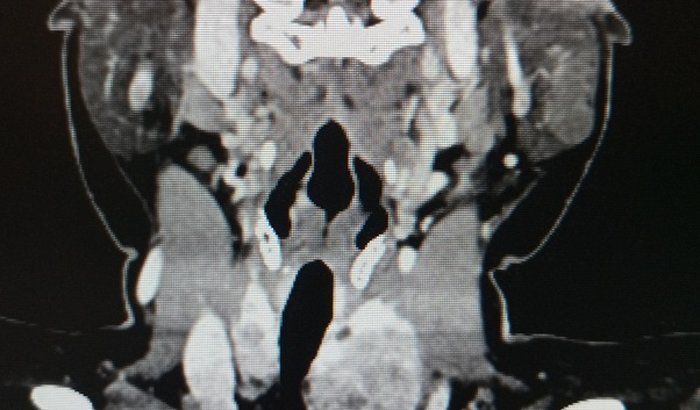

Estive por um ano em uma fila para retirada de um tumor na glandula parótida (salivar) e ela não aconteceu. Nos últimos 2 meses fui tomada por dores agudas e continuas que nenhum remédio ajuda, dificuldade de respirar, comer e dormir. Resolvi pedir meu prontuário médico e descobri que uma tomografia feita em janeiro já alertava que eu não tinha só um tumor, mas dois na glândula parótida e um bócio multinodular na tireóide que desviou minha traqueia que explica pq tudo tá tão difícil... mas esse diagnóstico foi omitido. Tamanha negligencia e descaso me levou a um estado preocupante e preciso de duas cirurgias delicadas pra remover esses tumores, inclusive preciso confirmar se sao benignos ou malignos. Nunca imaginamos ter uma urgência dessas, e, estamos tentando todas as formas pra chegar nesse valor, se vc pode ajudar com um real que seja, eu agradeço. 🙏